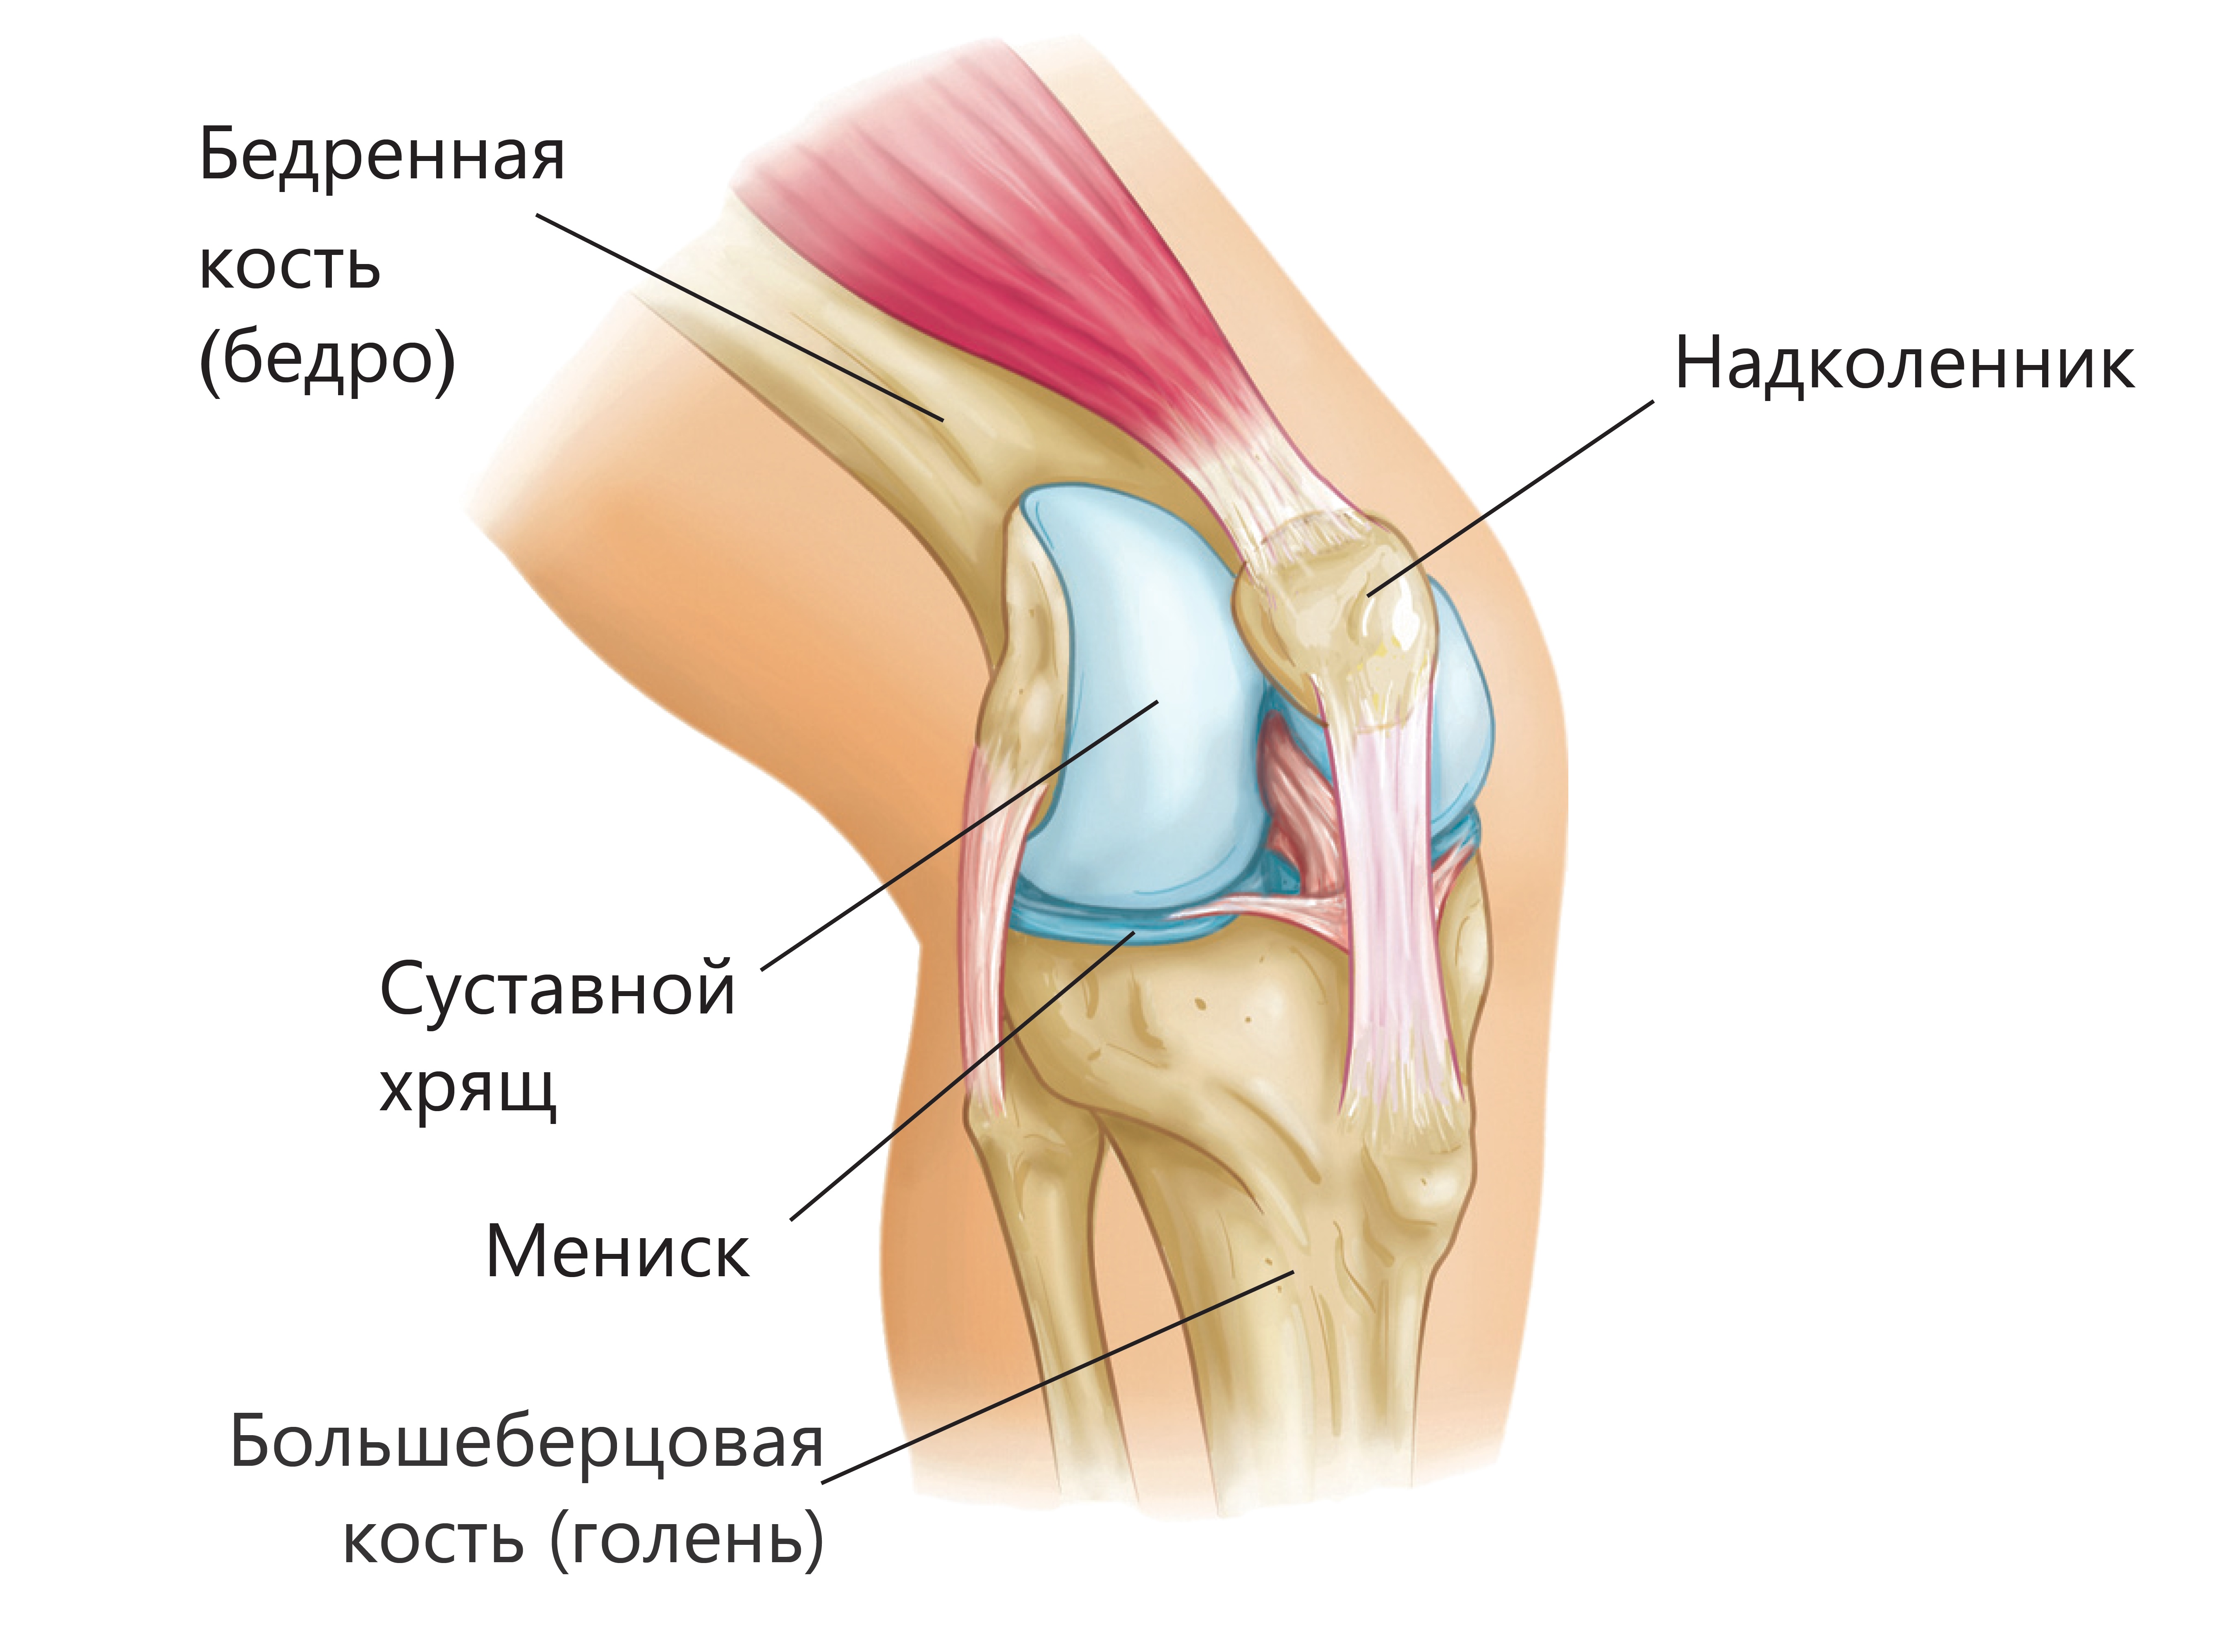

Заболевания и медицинские снимки: Жидкость в коленной чашечке